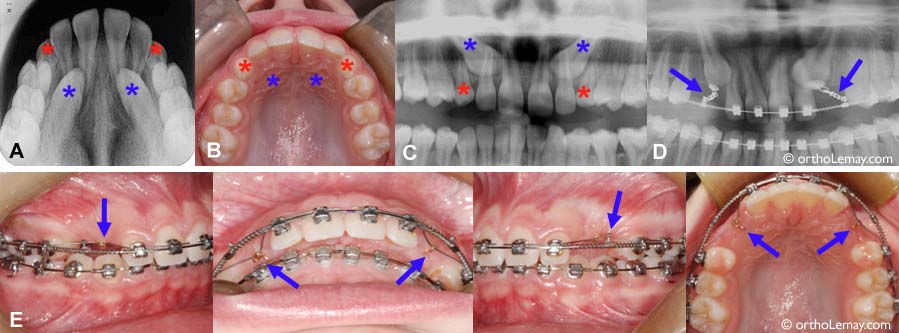

• (A) Une radiographie du palais montre la position anormale des canines (* bleu). Les canines temporaires sont toujours en place (* rouge) et ont probablement contribué à l’inclusion des canines pendant leur développement.

• (B) La muqueuse du palais présente de légères bosses qui laissent deviner la présence des canines du côté du palais. Ceci est une bonne indication de la position des canines avant même de prendre des radiographies.

• (C) La radiographie panoramique montre à quel point les 2 canines sont aussi inclinées vers le centre et sont derrières les racines des incisives latérales.

• (D) Les canines temporaires ont été extraites. Les boîtiers ont été posés pour aligner les dents et ouvrir l’espace nécessaire pour loger les canines. Des attaches de traction et chaînettes ont été collées sur les canines incluses. La traction est débutée et les canines commencent à se redresser à mesure qu’elles se dirigent vers l’arcade dentaire.

• (E) En bouche, tout ce qui est visible est le bout des chaînettes (flèches) dans lesquelles passe un fil flexible qui exerce une légère force de traction. À mesure que la canine descend, la chaînette sort de la gencive et sera progressivement coupée jusqu’à ce que la canine perce. À ce moment, une attache régulière (boîtier) sera collée pour compléter le déplacement des canines. Cela peut prendre de quelques mois à plus d’une année pour descendre des canines incluses jusqu’à leur position finale.